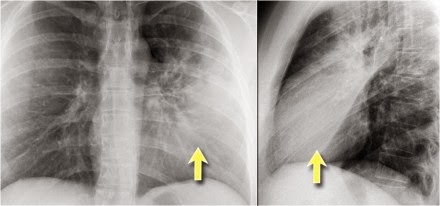

Notice that there is quite some lung volume below the dome

of the diaphragm, which will need your attention (arrow)

Here an example

of a large lesion in the right lower lobe, which is difficult to detect on the PA-film, unless when you give special attention to the hidden areas.

Here a pneumonia which was hidden in the right lower lobe mainly below the level of the dome of the diaphragm (red arrow).

Notice the increase in density on the lateral film in the lower vertebral region.

You may have to enlarge the image to get a better view.